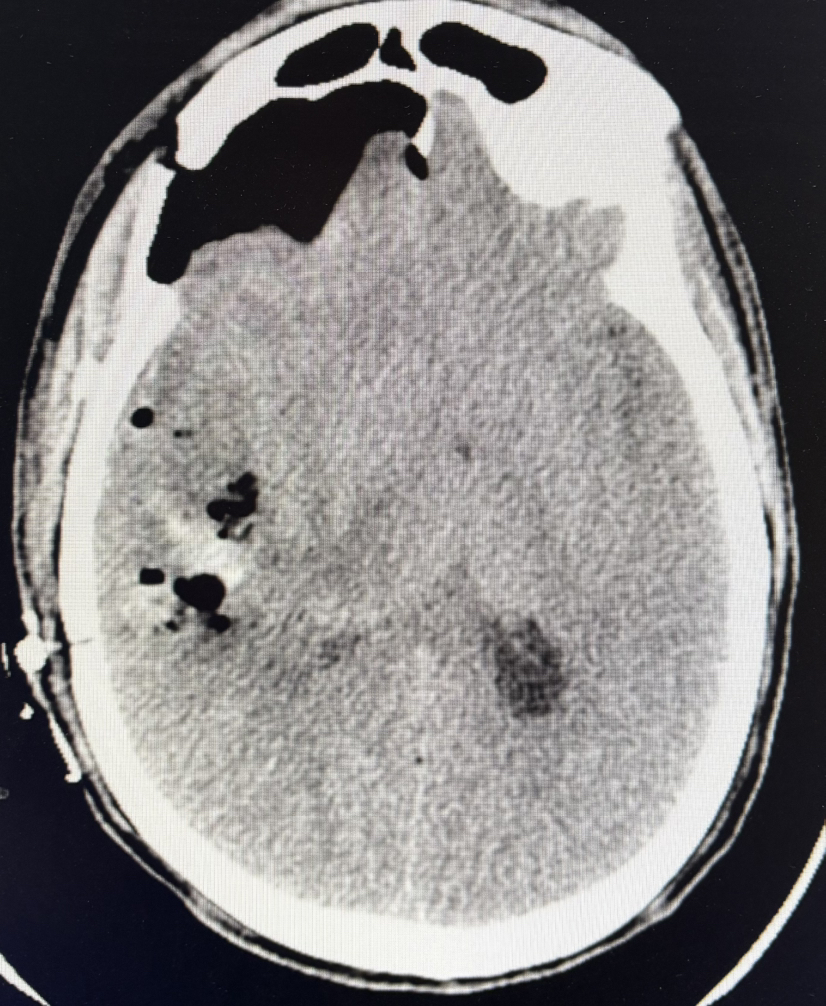

CT示:脑出血